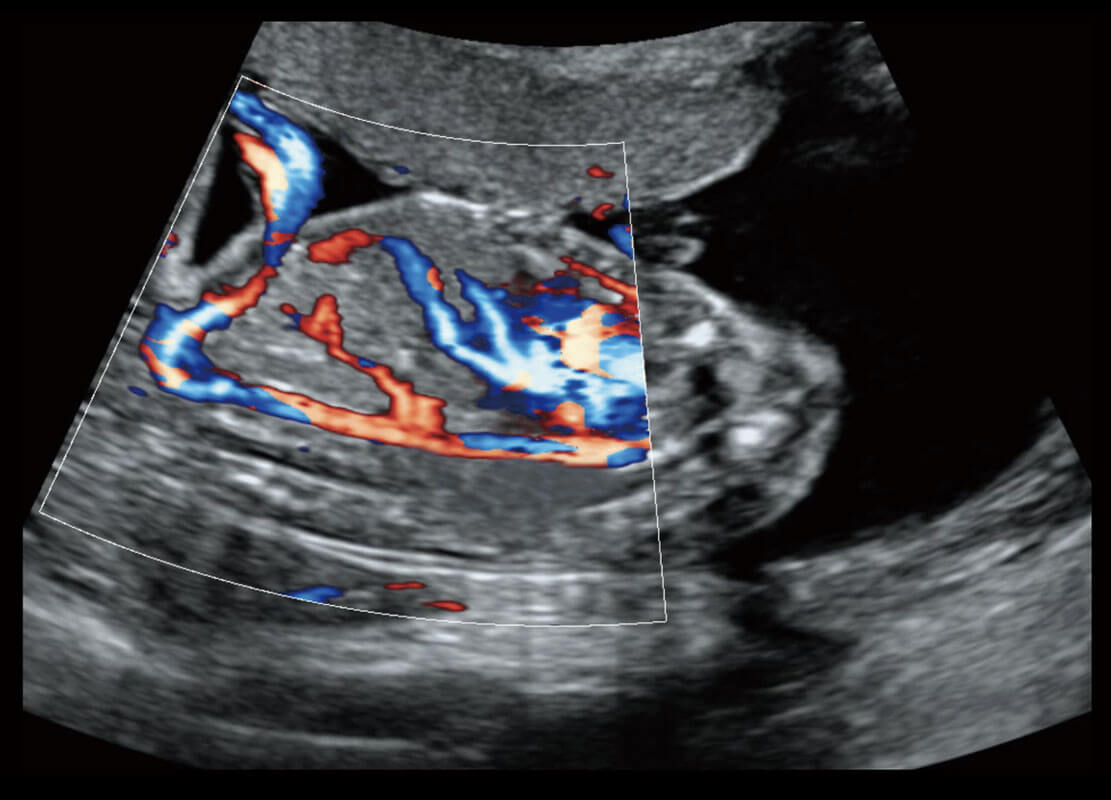

• 腔内三维-宫内节育器

• 腔内三维-光影成像